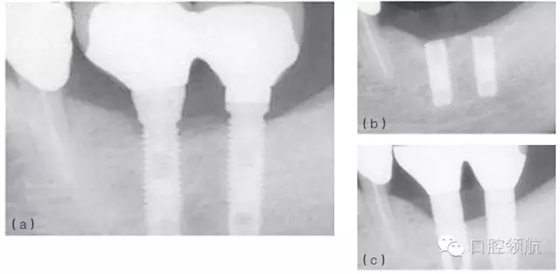

例如,在發(fā)生率低的種植體折斷病例中,感染和創(chuàng)傷經(jīng)常同時(shí)存在,或相繼發(fā)生。感染引起的種植體周骨喪失(種植體周圍炎)也可能導(dǎo)致種植體折斷。過(guò)載或創(chuàng)傷則是種植體折斷的第二個(gè)因素,種植體折斷的高度常常與骨-種植體的接觸水平相一致(圖6.4a~c)。也可相反,種植體周感染繼發(fā)于咬合創(chuàng)傷,導(dǎo)致種植體不能形成骨結(jié)合而失敗。(圖6.5a~c)

圖6.4 (a)18號(hào)、19號(hào)位點(diǎn)種植體出現(xiàn)邊緣骨吸收。(b)2年后出現(xiàn)折斷。(c)拔除了舊的種植體,新的種植體植入并進(jìn)行修復(fù)。